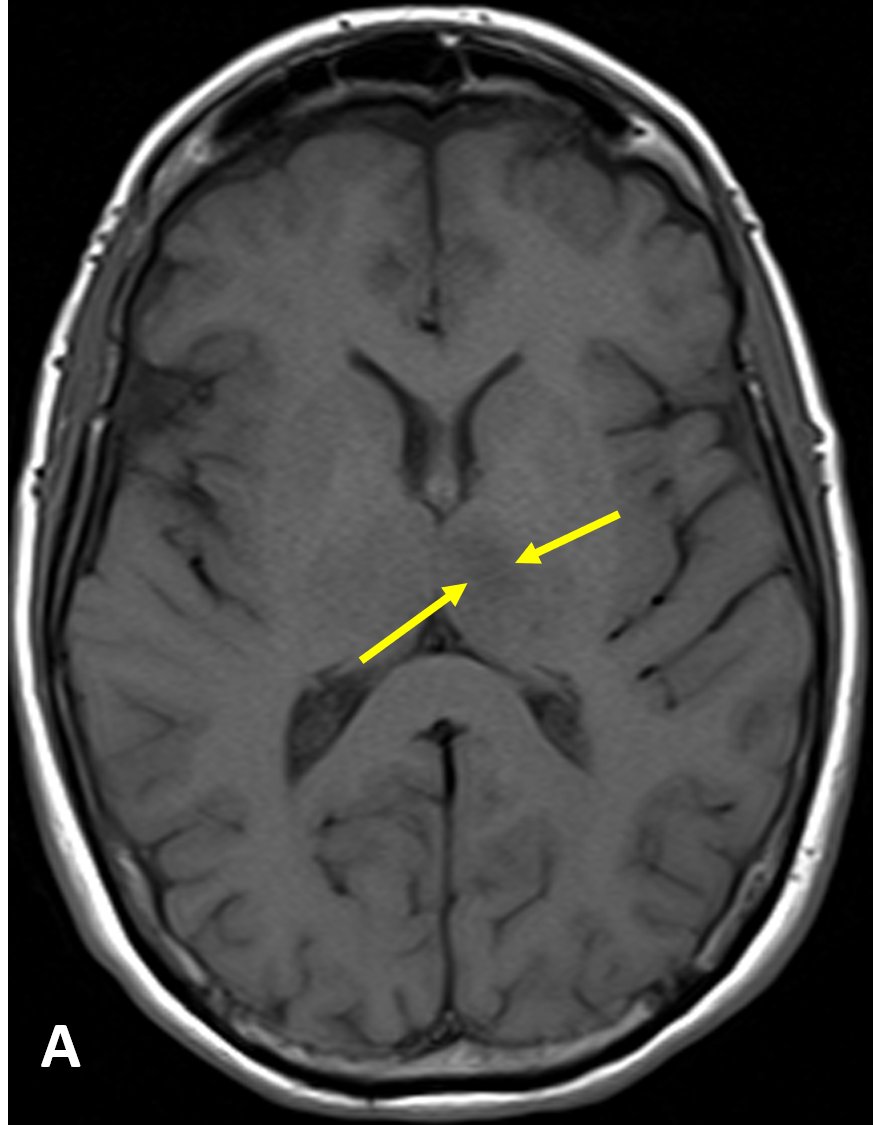

Acute Infarct - https://hubs.ly/H0mS5JB0 by

@jannimd There are two main types of stroke: ischemic (most common) due to lack of blood flow from thrombosis, embolism, systemic hypoperfusion, or cerebral venous sinus thrombosis, and hemorrhagic, due to bleeding#RadRes#FOAMRadpic.twitter.com/81UKvjKLOS